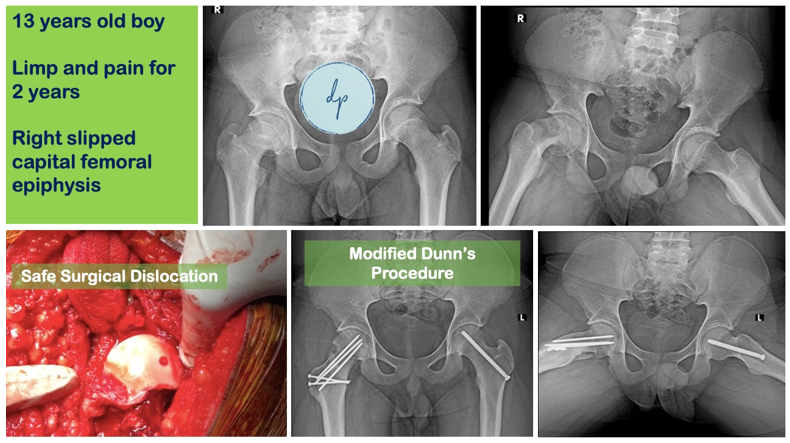

- Slipped Capital Femoral Epiphysis (SCFE)

- Modified Dunn’s procedure for SCFE